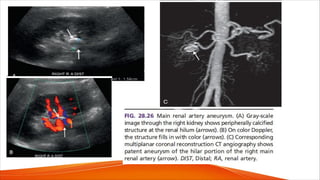

FIG. 28.27 Fibromuscular dysplasia.

(A) Gray-scale image demonstrates

multiple saccular dilatations

(solid arrows in A) in the hilar portion of

the main renal artery.

(B) Color Doppler image shows

disturbed flow and aliasing at the areas

of narrowing (dashed arrows in B)

between the aneurysmal

dilatations (solid arrows in B).

(C and D) Pulsed Doppler waveforms

from the narrowed segments show

elevated peak systolic velocities (PSV,

235 cm/s in C; 267 cm/s in D)

compatible with focal

stenoses. DIST, Distal; RRA, right renal

artery